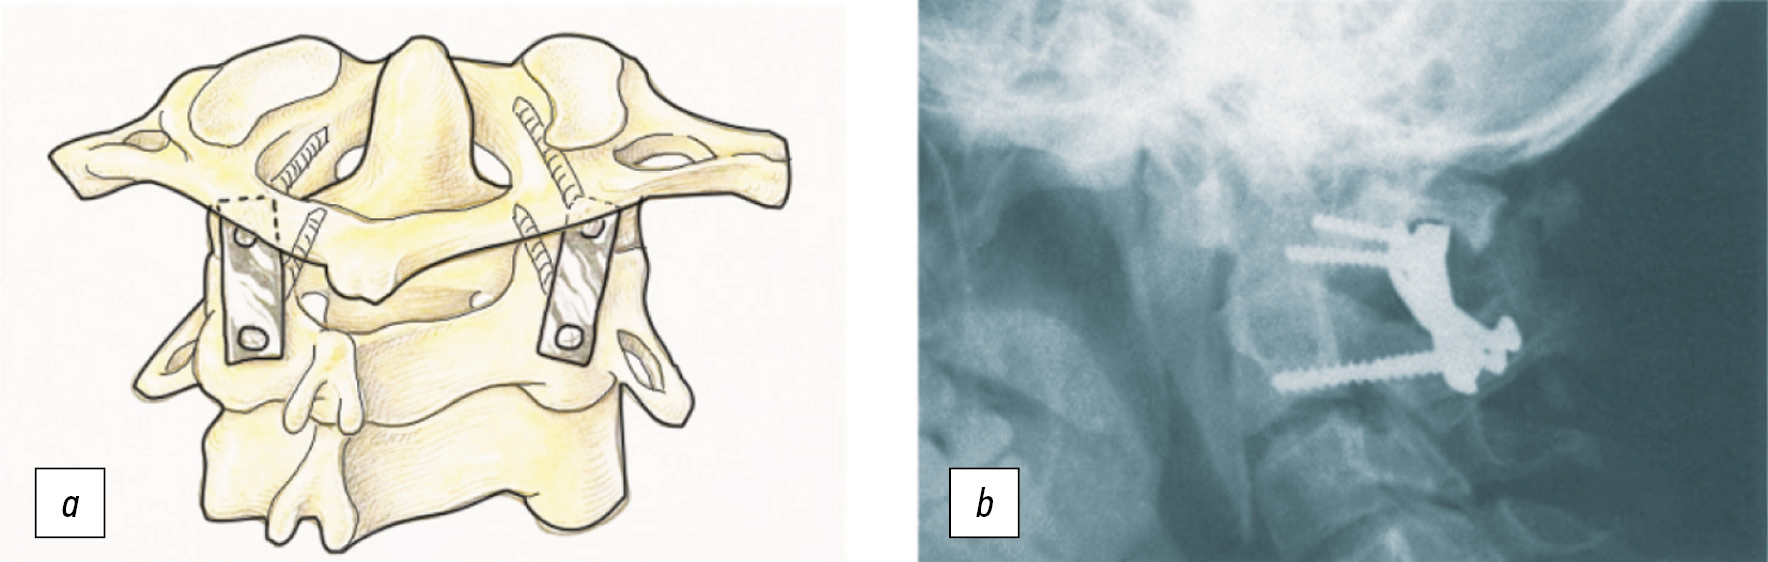

A.H. Menezes в 2008 г. сообщил об обширном опыте использования трансорального доступа у 733 пациентов, из которых у 30 был дистопический вариант зубовидной кости. Расположенная на средней линии зубовидная кость особенно хорошо подходит для выполнения данного доступа [38].

С другой стороны, последовательный, пошаговый релиз передних структур при этом доступе позволяет выполнить редукцию фиксированной ранее деформации, устраняя необходимость в субтракционном манёвре. Эти шаги включают релиз m. longus colli, m. longus capitis, передней продольной связки, спаек СI-СII сустава, передней дуги СI и, наконец, апикальной и крыловидных связок [3].

А.Н. Шкарубо, А.А. Кулешов с соавт. в 2016 г. описали клинический случай пациента с редким сочетанием зубовидной кости с солитарной костной кистой второго шейного позвонка и самой зубовидной кости. Пациенту было выполнено многоэтапное оперативное лечение, включающее дорсальную стабилизацию в виде окципитоспондилодеза, трансоральное удаление кисты из тела СII позвонка и последующее трансоральное удаление зубовидной кости с солитарной костной кистой [21].

Для выполнения передней декомпрессии путём резекции зубовидного отростка может использоваться эндоскопический эндоназальный доступ.

Впервые в мире эндоскопическое эндоназальное удаление инвагинированного зубовидного отростка позвонка СII (одонтоидэктомию) выполнил в 2005 г. американский нейрохирург A. Kassam, а в России впервые подобная операция была выполнена А.Н. Шкарубо в НМИЦ нейрохирургии им. акад. Н.Н. Бурденко в 2010 г. (рис. 7) [22].

Рис. 7. a — схема эндоскопического эндоназального доступа и удаления зубовидного отростка СII позвонка, b — состояние после эндоскопической трансназальной резекции инвагинированного зубовидного отростка и декомпрессии стволовых структур, c — костные структуры области краниовертебрального перехода, d — резекция переднего полукольца СI позвонка, e — резекция зубовидного отростка СII позвонка, части тела СII позвонка и нижних отделов ската.

Fig. 7. a — scheme of endoscopic endonasal approach and removal of the C2 dens, b — condition after endoscopic transnasal resection of invaginated C2 dens and decompression, c — CVJ bone structures, d — resection of the anterior half ring of the C1, e — resection of C2 dens, part C2 body and the lower parts of basion.

S. Magrini с соавт. в 2008 г. описали эндоскопическую эндоназальную одонтоидэктомию у пациента с синдромом Дауна, зубовидной костью и клиникой прогрессирующего тетрапареза с дыхательными нарушениями. Послеоперационный период протекал без осложнений. Через 2 месяца интенсивной физиотерапии отмечалось улучшение неврологической симптоматики в виде увеличения мышечной силы с 2 до 4 баллов и исчезновения дыхательных расстройств [39].